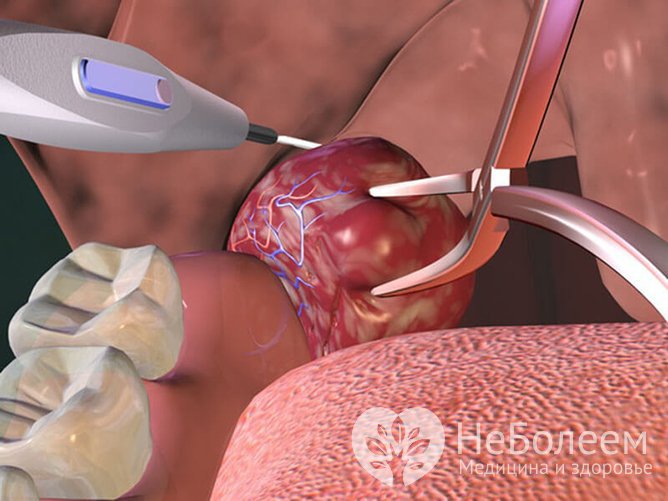

В случае необходимости проводится оперативное вмешательство

В случае необходимости проводится оперативное вмешательствоПоказания для тонзиллэктомии:

- гнойные ангины, которые возникают чаще, чем раз в три месяца;

- нарушение дыхания из-за увеличенных миндалин;

- отсутствие эффекта медикаментозной терапии;

- наличие осложнений: артрита, миокардита, пиелонефрита.

Альтернативой удалению миндалин является прижигание лазером, жидким азотом или электрокоагуляция пораженных участков. При этом хронический воспалительный процесс устраняется, а гланды продолжают выполнять свои функции в полном объеме.

Противопоказания к проведению тонзиллэктомии:

- нарушение свертываемости крови;

- патологии сердца и сосудов;

- сахарный диабет;

- активная фаза туберкулеза.